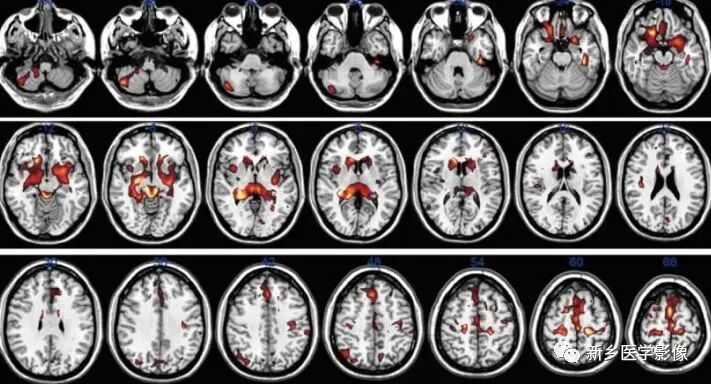

本次研究老师们通过16个问题的测试把48名同学分成了手机依赖症组25名,正常组23名。使用3.0T磁共振进行对48名在校大学生进行了扫描,并对大脑关键区域:中央前回、旁中央小叶、额上回、眶额部皮层、背侧前扣带回、岛叶、基底节区的尾状核、壳核、苍白球、杏仁核和丘脑、伏隔核、中脑腹侧被盖区、海马等进行了深入的分析。

1.手机依赖者大脑中的一些部位的体积显著低于正常组,这些部位包含了决策与情绪加工、管理相关的部分边缘系统和纹状体区; 冲动控制相关的中央前回、旁中央小叶、额上回、眶额部皮层、岛叶、背侧前扣带回灰质区。

2.手机依赖者与决策能力、冲动控制能力相关脑区受损。

手机依赖者的前额叶及背侧前扣带回体积显著低于正常对照组, 在物质成瘾中扣带回体积的减小较为常见,作为执行控制网络的重要组成部分,之前大量的物质成瘾研究已证明扣带回具有认知功能、情感调节和自我控制的功能。背侧前扣带回体积显著低于正常对照组,它是手机依赖者冲动控制能力受损的神经基础。前额叶和岛叶是与决策行为密切相关的脑区, 这些脑区的改变与网络成瘾个体受损的决策能力相关 。

3.手机依赖者与奖赏、情绪加工管理相关脑区受损

本研究中海马、中脑腹侧被盖区、岛叶、杏仁核、伏隔核及基底节区的尾状核、壳核、苍白球体积显著低于正常对照组, 这些脑区被认为是与奖赏及情绪加工管理密切相关的区域。

它们一旦受损,手机依赖者极可能会导致大脑奖赏回路对正常的自然奖赏信号的敏感性降低, 导致个体对自然奖赏缺乏应有的兴趣,进而从自然奖赏中已无法获得愉悦感;手机的便捷性与多功能性恰好能够为大学生们提供一个虚拟的环境为他们获取愉悦感, 以释放在现实生活中的不满情绪与压力; 手机的虚拟世界能够满足他们的心理需求,最终导致对手机的依赖。